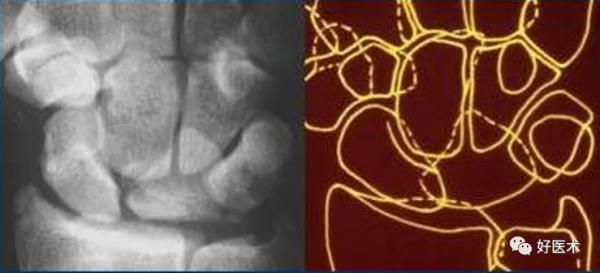

a. M形腕掌線 b. 腕骨弧線(Gilula線)

若顯示腕骨弧線不連續或各弧線不平行,或腕掌線M形結構消失,應高度懷疑腕關節不穩或脫位。

3.腕骨弧線

- 弧線Ⅰ為沿舟骨、月骨、三角骨近側凸面的光滑曲線。

- 弧線Ⅱ為其遠側凹面的光滑曲線。

- 弧線Ⅲ為頭狀骨和鉤骨近側的曲面。

腕骨弧線中斷

弧線中斷提示骨折或韌帶斷裂導致的半脫位或脫位。

上圖顯示弧線 Ⅰ 在月骨-三角骨關節處的中斷。

弧線 Ⅱ 中斷於舟月關節和月骨-三角骨關節(上圖)。弧線 Ⅰ 雖有缺口但仍呈光滑弧線,可認為是完整的。

弧線 Ⅲ 中斷,上圖顯示頭狀骨-鉤骨關節異常階梯狀改變。